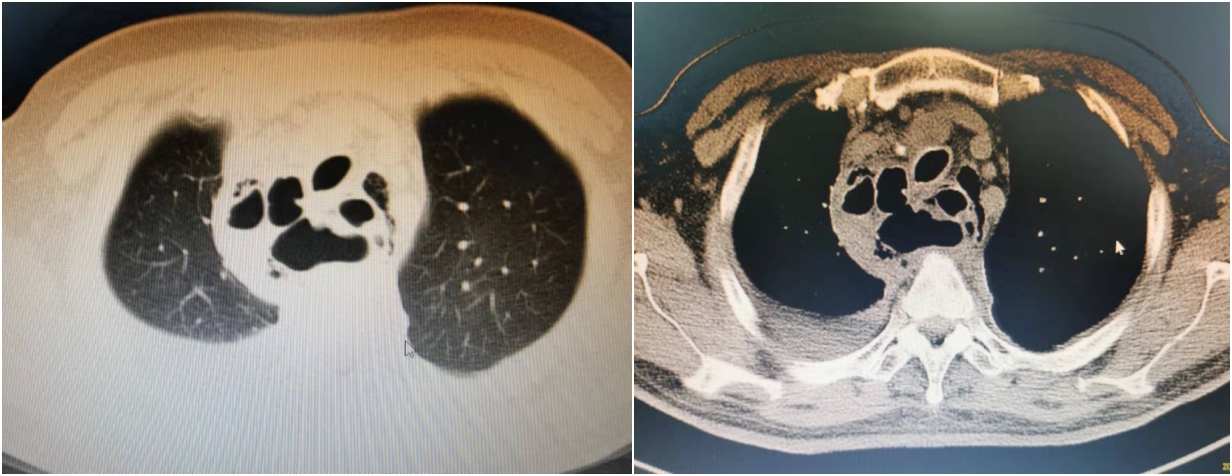

患者付某,男,59岁,凤凰县人,因“反复胸痛、胸闷15天,虚汗、四肢无力1天”急诊来我院就诊,急诊胸部CT显示:上中下纵隔不规则软组织包块,考虑纵隔脓肿可能;胸段食管扩张,食管纵隔瘘形成可能;纵隔气肿。经主治医师张建军会诊后收住心胸外科。

术前CT显示纵膈内大血管、气管、食管间隙广泛气肿并存液气平面

治疗后复查CT示纵膈结构清晰可见